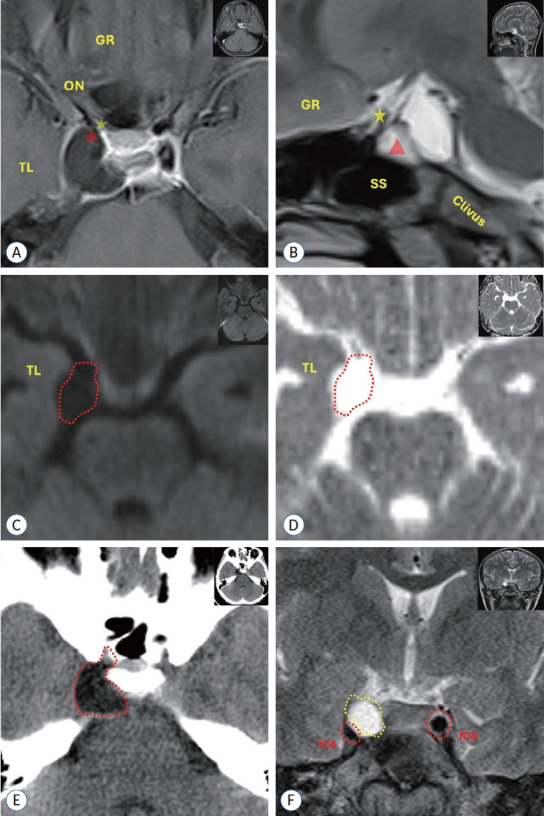

单眼突然视力丧失的原因包括孤立性眼病、血管病变和视神经压迫。本文报告一例寄生虫病(细粒棘球绦虫)因视神经压迫导致突然视力丧失。据我们所知,这是第一例报道的包虫囊肿通过视颈三角形延伸到视神经管的儿童患者。一名12岁女孩因视力恶化1周就诊于眼科。检查显示她右眼视力下降。检查未发现眼部异常,颅脑成像显示右侧视神经受压病变,患者转至神经外科。经颅穿刺抽吸内容物后,显微镜下外观类似表皮样瘤的亮白色病变被完全切除。病理报告为包虫囊肿。儿童突发性视力丧失的鉴别诊断应考虑侵犯视神经管的包虫病;然而,它仍然是发展中国家的一个重要健康问题。在不破裂的情况下对囊肿包膜进行细致的切除是手术治疗成功的保证。

The causes of sudden vision loss in one eye include isolated eye diseases, vascular pathologies, and optic nerve compression. This report highlights a case of parasitosis (Echinococcus granulosus) causing sudden vision loss due to optic nerve compression. To our knowledge, this is the first reported case of a hydatid cyst extending into the optic canal through opticocarotid triangle in a pediatric patient. A 12-year-old girl presented to the ophthalmologist with progressive visual deterioration over a period of 1 week. Examination revealed reduced visual acuity in her right eye. No ocular abnormality was detected on examination, cranial imaging revealed a lesion compressing the right optic nerve and the patient was referred to neurosurgery. The bright white lesion with a microscopic appearance resembling an epidermoid tumor was completely excised after aspirating the contents with transcranial access. Pathology was reported as hydatid cyst. Hydatid cysts invading the optic canal should be considered in the differential diagnosis of sudden visual loss in the pediatric age group; however, it continues to be an important health problem in developing countries. Meticulous excision of the cyst capsule without rupture ensures the success of surgical treatment.